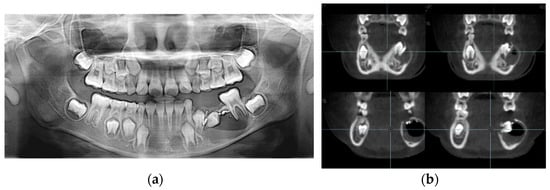

An 8-year-old girl was referred to the Department of Pediatric Dentistry of Kyung Hee University Dental Hospital at Gangdong from a local dental clinic for the treatment of a cystic lesion in the left mandibular primary molar area. Her medical history was unremarkable. According to the referral from the local dental clinic, her dental history was a pulpectomy with root canal filling with Vitapex® and restoration with a stainless-steel crown on the left mandibular primary molar 3 years ago. An endodontic retreatment was performed due to a recurrent periapical abscess that occurred 16 months after the initial treatment at the local clinic. Nevertheless, due to the residual periapical lesion and severe tooth mobility, the teeth were extracted one year after the retreatment at the local clinic. Radiological examination revealed a well-defined osteolytic lesion involving the premolars and radiopaque overfilling materials (Vitapex®) around the involved premolars (Figure 4a). Cone-beam computed tomographic (CBCT) view, cortical bone thinning, and expansion of the lesion were observed (Figure 4b).

Figure 4.

Initial visit: (a) panoramic radiograph; (b) cone-beam computed tomography. The cystic lesion around the successive left mandibular premolars can be seen, and extruded canal filling materials are also observed.